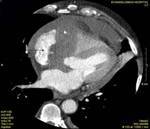

Methods: Twenty-two patients referred to our department with a suspected cardiac mass, previously detected by cardiac ultrasound, were evaluated by CT (12 patients) and MRI (4 patients). Six patients were examined by both modalities. In 2 cases of staging of a known primary neoplasm and one case of a suspected epicardiac lesion, positron emission tomography (PET-CT) was performed. The CT cardiac examinations were performed using a 16-slice multislice scanner with ECG gating. The MRI examination was performed on a 1.5 Tesla MRI scanner using an ECG-gated cardiac protocol and the PET-CT examination was performed on an integrated PET-CT four-slice scanner, using 370 mMBq of fluorodeoxyglucose.

Results: Twenty-two cardiac masses were successfully detected and their characteristics adequately delineated, including eight myxomas, one angiosarcoma, one ventricular lymphoma, one endocardiac metastasis, one epicardiac paraganglioma, and 10 cases of intracardiac thrombi.